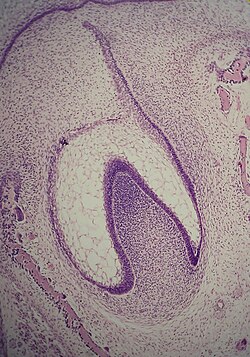

Rast i razvoj zuba prolazi kroz četiri stadij: stadij zametka, stadij kape, stadij zvona i stadij formiranja korijena.[1]

Stadij zametka počinje u šestom tjednu intrauterinog života ploda. Ektodermalni epitel zadebljava i formira epitelnu gredicu, koja se razvija i spušta u dubinu mezoderma. Ona se dijeli na vanjski i unutrašnji segment (primarna dentalna lamina) na kojem se u osmom tjednu počinju formirati zameci prvih mliječnih zuba (koji su ujedno i caklinski organ).

U stadiju kape započinje kalcifikacija caklinskog organa, proliferacija epitelnih stanica zametka u okolni mezoderm i invaginacija bazalnog dijela caklinskog organa.

U stadiju zvona se nastavlja proliferacija epitela i produbljivanje invaginacije u bazalnom području caklinskog organa. U udubljenje urasta mezoderm i formira dentalnu papilu, od koje će nastati zubna pulpa. Od mezenhimnih stanica razvija se folikularna vrećica, koja sa dentalnom papilom i caklinskim organom čini zubnu klicu.

Zubna pulpa sa periferno raspoređenim odontoblastima započinje stvaranje dentina (dentinogeneza), a caklinski organ pomoću ameloblasta stvaranje cakline (amelogeneza). Folikularna vrećica formira fibrovaskularnu kapsulu oko zuba u razvoju, koja je odgovorna za nutriciju, a ima i druge važne uloge. Na kraju stadija zvona počinje stvaranje kosti u mezodermu, folikul se transformira u periodontalno tkivo, a od caklinskog organa nastaje sekundarna dentalna lamina (za supstituentne zube). Također caklina i dentin formiraju zonu koja će postati caklinsko-dentinski spoj.

Stadij formiranja korijena se karakterizira stvaranjem strukture korjenova od Hertvigove epitelne ovojnice, koja nastaje u stadiju zvona od unutrašnjeg sloja caklinskog organa.